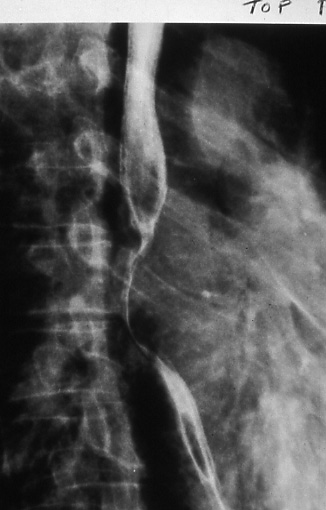

Fig. 26b: Barium swallow showing the displacement of the esophagus by the subcarinal nodes, N2. The presence of the nodes can only be inferred.